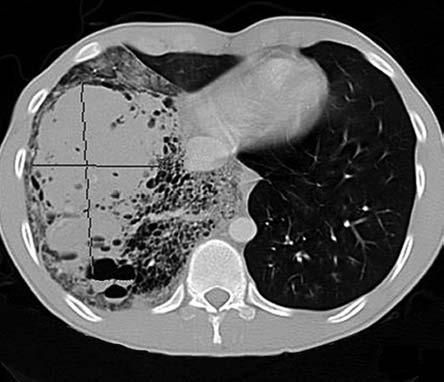

A CT scan of the chest showed a right hemothorax, a lower lobe mass that extended to the middle lobe, cystic areas surrounding the mass, and what appeared to be a vessel coming off the descending aorta adjacent to the celiac axis and feeding into the mass (Figure 2). After bronchoscopy failed to control the bleeding, urgent aortic angiography with subsequent embolization of the feeding artery was performed, and the crisis abated (Figure 3).

Figure 2 – This CT scan shows a right hemothorax, a lower lobe mass extending to the middle lobe, cystic areas surrounding the mass, and what appears to be a vessel coming off the descending aorta adjacent to the celiac axis and feeding into the mass.